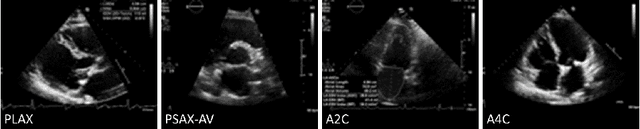

Abstract:We propose a new method to automatically contour the left ventricle on 2D echocardiographic images. Unlike most existing segmentation methods, which are based on predicting segmentation masks, we focus at predicting the endocardial contour and the key landmark points within this contour (basal points and apex). This provides a representation that is closer to how experts perform manual annotations and hence produce results that are physiologically more plausible. Our proposed method uses a two-headed network based on the U-Net architecture. One head predicts the 7 contour points, and the other head predicts a distance map to the contour. This approach was compared to the U-Net and to a point based approach, achieving performance gains of up to 30\% in terms of landmark localisation (<4.5mm) and distance to the ground truth contour (<3.5mm).